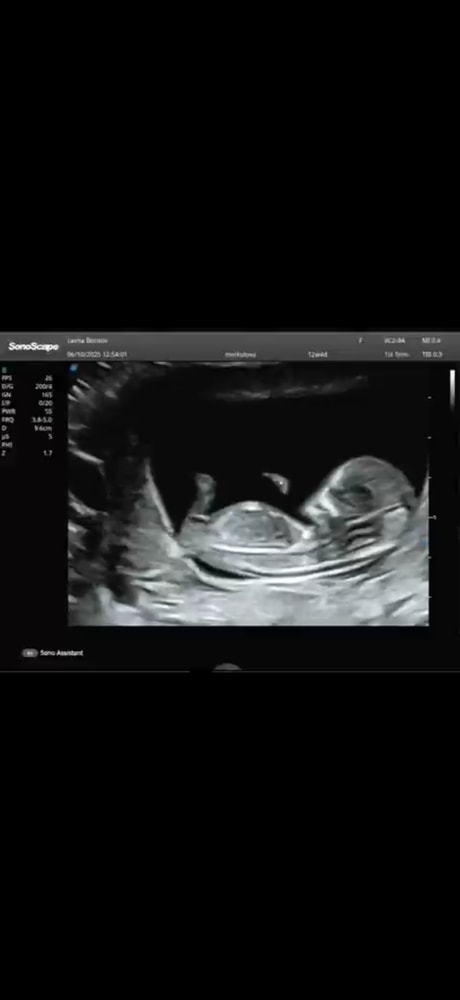

Подскажите на кого похоже ? Мальчик или девочка ?

Пол малышаСрок 12 недель . Скрины с видео , при разном ракурсе половой бугорок меняется